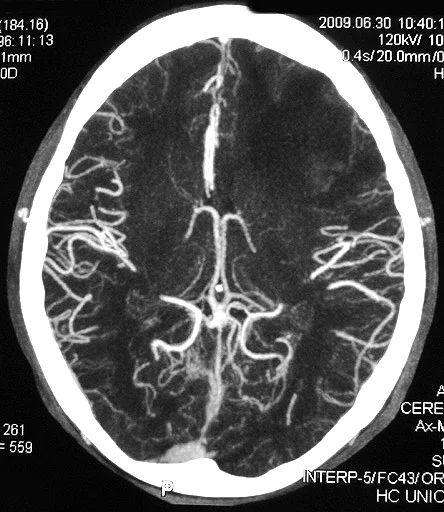

Descubra Tudo sobre Angio Tomografia: O Guia Completo para Saúde Vascular”

A Angiotomografia: Ferramenta Essencial no Diagnóstico Moderno Você já se perguntou como os médicos conseguem visualizar o interior do corpo humano sem fazer uma única incisão? A resposta está na evolução das tecnologias de imagem, como a angiotomografia. Este exame tornou-se vital no diagnóstico de inúmeras condições vasculares, permitindo que especialistas vejam vasos sanguíneos em … Ler mais